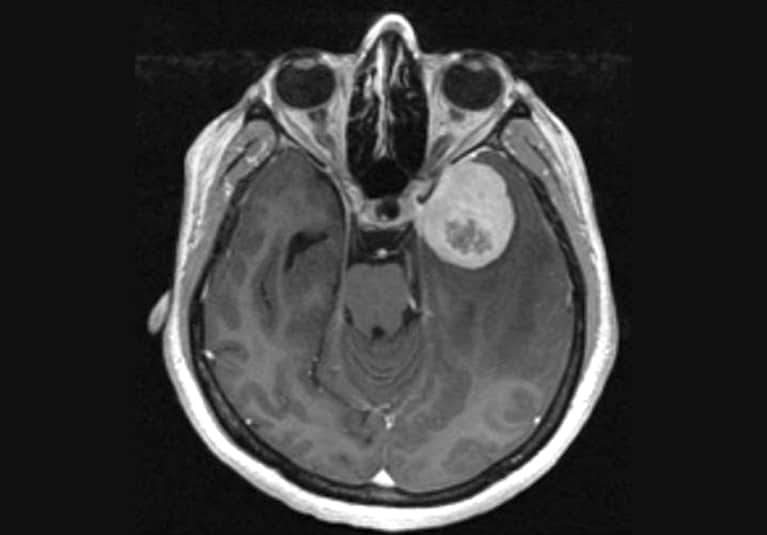

Researchers co-led by a Mayo Clinic Neurosurgery chair have demonstrated that telomerase reverse transcriptase (TERT) gene expression in meningiomas predicts earlier disease progression, independent of TERT promoter mutations (TPMs) and other markers.

The study, which retrospectively examined clinical and molecular data from 1,241 meningiomas, is the first comprehensive investigation of TERT RNA expression and associated clinical outcome in a multi-institutional cohort of meningiomas. As described in The Lancet Oncology, the researchers analyzed 380 meningiomas from a single center and a validation cohort of 861 meningiomas from institutions across the U.S., Canada and Germany.